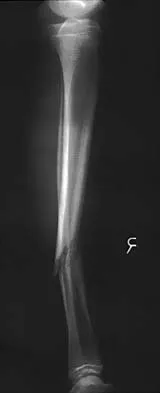

Question 209High Yield

A 20-year-old man sustained a closed tibial fracture and is treated with a reamed intramedullary nail. What is the most common complication associated with this treatment?

Explanation

The most common complication is anterior knee pain (57%). The knee pain is activity related (92%) and exacerbated by kneeling (83%). Although knee pain is the most common complication, most patients rate it as mild to moderate and only 10% are unable to return to previous employment. Some authors report less knee pain with a peritendinous approach when compared to a tendon-splitting approach. In one study, nail removal resolved pain in 27%, improved it in 70%, and made it worse in 3%. The incidence of the other complications was: infection 0% to 3%, nonunion 0% to 6%, and malunion 2% to 13%. Compartment syndrome is rare after nailing. Court-Brown CM: Reamed intramedullary tibial nailing: An overview and analysis of 1106 cases. J Orthop Trauma 2004;18:96-101. McQueen MM, Gaston P, Court-Brown CM: Acute compartment syndrome: Who is at risk? J Bone Joint Surg Br 2000;82:200-203.